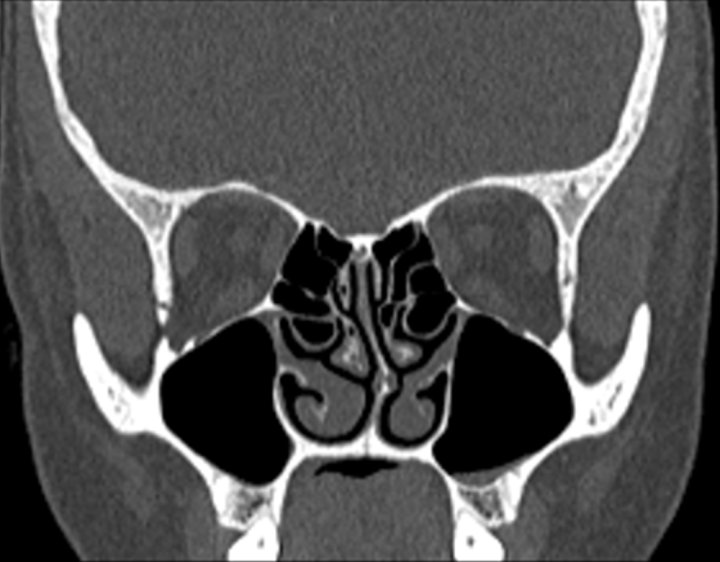

Click any image for labels.